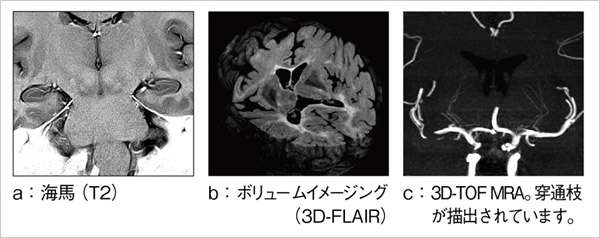

●海馬領域の高分解能画像

3Tでは,S/Nが高くなることから,高分解能で撮像しても鮮明な画像を得ることができます。これにより,海馬の詳細な構造を描出することができます(図2 a)。

●ボリュームイメージング

3Tでは,高いS/Nを利用してボリュームで撮像することができます。解析に必要なボリュームデータを,短時間で高精細に得ることができます(図2 b)。

●穿通枝まで描出するMRアンギオ

磁場強度が上がることによって,MRアンギオの描出が向上します。高分解能撮像と背景信号の抑制効果により,穿通枝のような細かい血管でも描出できる可能性が広がります(図2 c)。

図2 3T MR画像